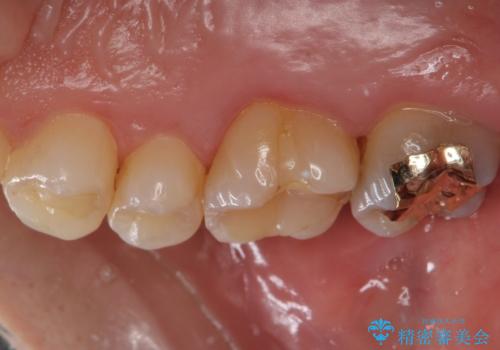

- 奥歯の劣化・変色した樹脂の詰め物をやり直していきます。

セラミックのインレーでは強度に不安が残るため、セラミッククラウンで全体を被覆することとしました。

- 右上6:仮歯+ジルコニアクラウン/11,000円+110,000円費用は治療当時の料金となります